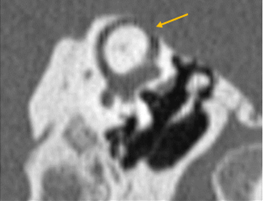

Dehiscencia del canal semicircular superior

Es debido a un defecto óseo del techo del conducto semicircular superior (CES), que crea una comunicación con la fosa craneal media y la duramadre. Puede producir un síndrome de tercera ventana del laberinto óseo, el cual se asocia con signos vestibulares como vértigo o mareo al exponerse a sonidos fuertes, también llamado fenómeno de Tullio. Además puede producir hipoacusia mixta con reflejo estapedial conservado. En ocasiones puede asociarse a otosclerosis (Fig. 9).

![]() |

Figura 9. Dehiscencia de canal semicircular superior. Reconstrucción de Poshi (Izquierda) y Reconstrucción de Stenver (Derecha) |